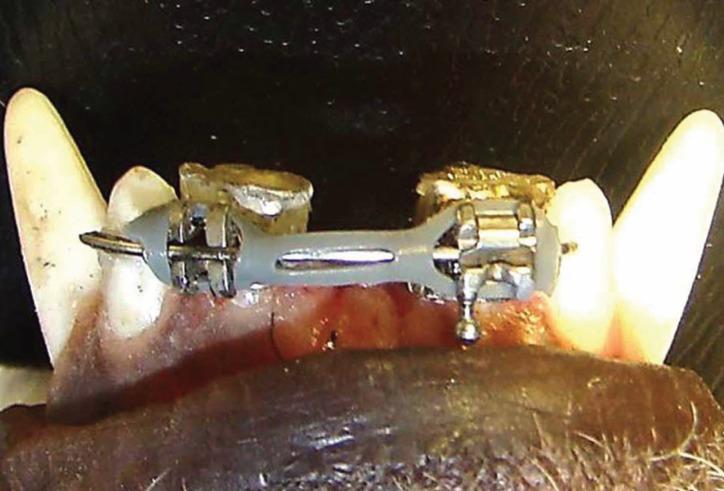

The experiments were conducted in 20 male dogs. Bands were cemented in all intermediate incisors, with conventional brackets (Morelli) on the right side and hybrid self-ligating ones (T3-American Orthodontics) on the left side. A 0.019" x 0.025" stainless steel wire was inserted passively in the slot of these brackets with chain elastics (250 gf) to perform sliding mechanics. Clinical records of the orthodontic mechanics were made before and after 15 days of the tooth movement. The dental segments of the animals were prepared for light microscopy. Statistical analysis of variance and the Tukey correction with a P value at 5% were used.

实验在20只雄性犬身上进行。在所有中切牙上粘结带环,右侧使用传统托槽(Morelli),左侧使用混合型自锁托槽(T3 - 美国正畸公司)。一根0.019英寸×0.025英寸的不锈钢丝被动插入这些托槽的槽沟中,并使用链状弹力圈(250 gf)进行滑动矫治力学操作。在牙齿移动15天前后记录正畸力学的临床数据。对动物的牙段进行光镜制备。采用方差分析和P值为5%的Tukey校正进行统计分析。